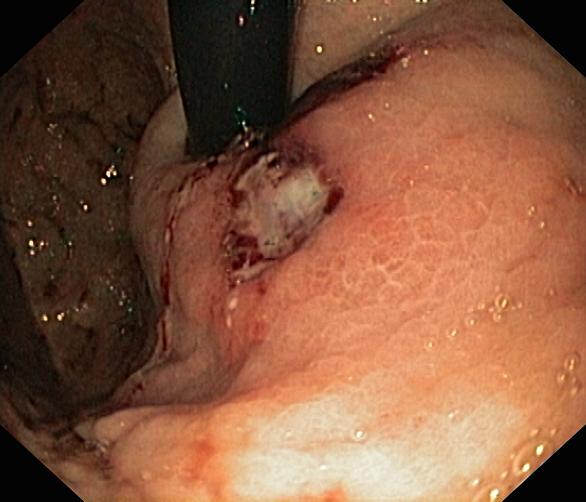

Krwawienie